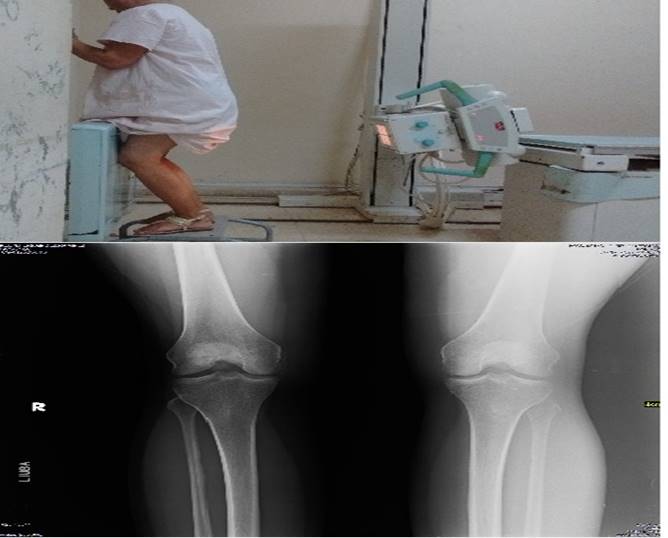

Para la evaluación del espacio articular de la rodilla, es de vital importancia realizar las vistas radiográficas adecuadas, dentro de las que resalta por su características la descrita por Rosenberg TD et al. 22) que consiste en colocar al paciente de pie con la rodilla flexionada en 45 grados, la inclinación del rayo es de alrededor de unos 10 grados con desviación cefalo-caudal, esta proyección permite identificar de forma adecuada el espacio articular (Figura 1). 23,24,25